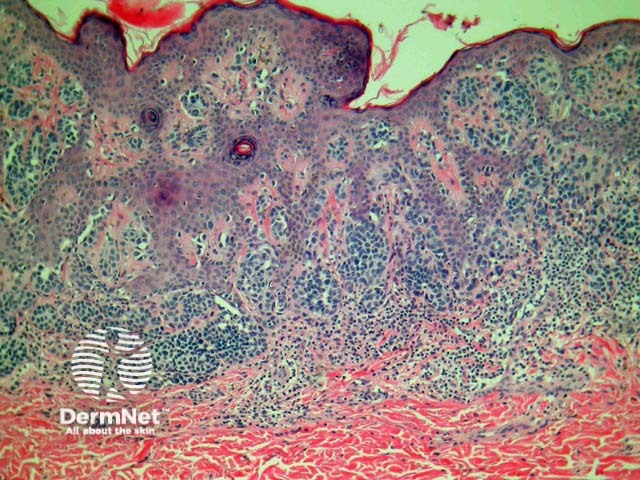

Junctional naevi are usually pigmented macules on clinical examination. Histologically, proliferating melanocytes are found at the dermoepidermal junction. Cells within nests are oval or cuboidal in shape, with clear cytoplasm and variable pigmentation (figure 1).

Figure 1